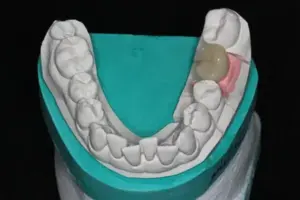

Jetzt bekommt das Zahnfleisch noch etwa 2 Wochen Zeit, schön um den Gingivaformer zu wachsen. Herr F. kommt nochmal für die Abdrucknahme mittels eines so genannten Abdruckpfostens, der anstelle des Gingivaformers auf den Implantat-Körper geschraubt wird. Mit diesem Übertragungspfosten kann im zahntechnischen Labor ein für Sie individuell passender Implantat-Aufbau und eine Implantat-Krone hergestellt werden. Siehe Bild 7.

Bild 7: individuell passender Implantat-Aufbau und Implantat-Krone